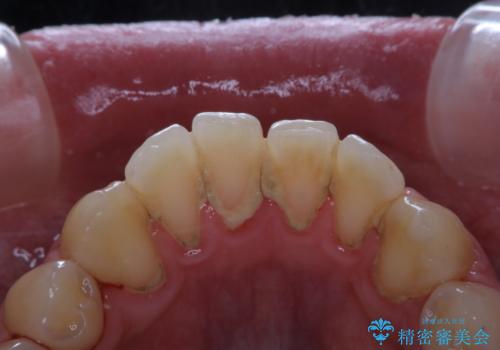

30代男性 PMTCで歯石取り

担当医 歯科衛生士